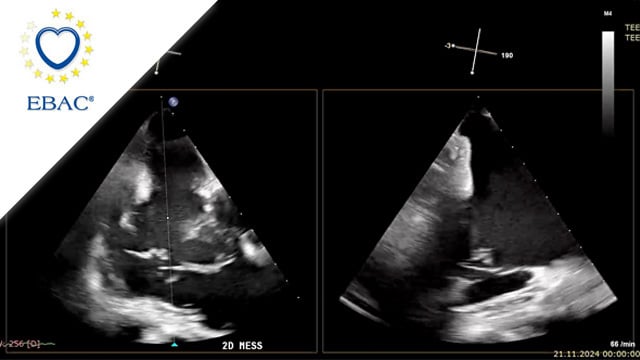

How should I manage a patient with insufficient surgical closure of the left atrial appendage

Incomplete surgical LAA closure: how would you proceed?

Despite prior closure with an Atriclip during CABG, transoesophageal echocardiography reveals a persistent LAA gap in a high-risk patient with recurrent bleeding.

Explore the clinical details, imaging, and treatment dilemmas—then share your management approach!